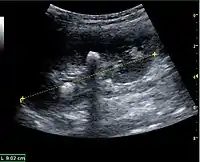

The length of the adult kidney is normally 10–12 cm, and the right kidney is often slightly longer than the left kidney. The adult kidney size is variable due to the correlation with body height and age; however, normograms for pediatric kidney size are available.[1]

Cortical thickness should be estimated from the base of the pyramid and is generally 7–10 mm. If the pyramids are difficult to differentiate, the parenchymal thickness can be measured instead and should be 15–20 mm (Figure 3). The echogenicity of the cortex decreases with age and is less echogenic than or equal to the liver and spleen at the same depth in individuals older than six months. In neonates and children up to six months of age, the cortex is more echogenic than the liver and spleen when compared at the same depth.[1]